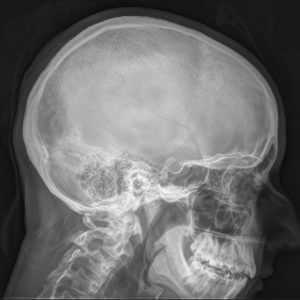

Информативность рентгенографии черепа в диагностике черепно-мозговых травм (ЧМТ) невысока. Однако этот метод исследования имеет несомненное значение при обследовании больных с переломами основания и свода черепа, опухолью гипофиза, врожденными пороками развития или родовой травмой, а также системными заболеваниями, приводящими к поражению костей черепа. Для получения более подробной информации при ЧМТ применяют КТ головы. Рентгенография черепа позволяет оценить состояние 3 групп составляющих его костей: костей свода черепа, нижней челюсти и костей лица. Кости свода черепа и лица неподвижно соединены друг с другом, образуя в месте соприкосновения зубчатую линию, которая называется черепным швом. Череп представляет собой столь сложную анатомическую структуру, что всестороннее его изучение требует выполнения нескольких рентгеновских снимков в различных проекциях.

При описании снимков рентгенолог оценивает размеры, форму, толщину и расположение костей черепа, а также сосудистый рисунок, состояние околоносовых пазух и черепных швов. Все перечисленные характеристики должны соответствовать возрасту пациента.

Рентгенографию черепа часто применяют для диагностики переломов основания или свода. Однако перелом основания черепа может остаться нераспознанным при высокой плотности костей. Исследование позволяет выявить врожденные аномалии развития черепа, а также увеличение размеров, эрозии или остеопороз турецкого седла, обусловленные повышением внутричерепного давления (ВЧД). Выраженная внутричерепная гипертензия (ВЧГ) может сопровождаться увеличением размеров головного мозга, который давит на внутреннюю пластинку черепа, оставляя на ней характерные знаки ("пальцевые вдавления"). При остеомиелите рентгенография черепа позволяет выявить очаги кальцификации костей черепа, при хронической субдуральной гематоме - внутричерепные кальцификаты. Кроме того, с помощью данного метода можно либо непосредственно диагностировать обызвествленные опухоли головного мозга (например, олигодендроглиомы или менингиомы), либо судить о наличии внутричерепных объемных образований по смещению обызвествленного шишковидного тела относительно срединной плоскости черепа. И наконец, на рентгенограммах черепа можно выявить другие изменения костных структур, характерные для метаболических нарушений (например, при акромегалии или болезни Педжета).

Рентгенографическое исследование черепа, как правило, начинается с производства двух обзорных снимков во взаимно перпендикулярных проекциях (в прямой и боковой), на которых должны быть видны все отделы черепа. По этим снимкам врач-рентгенолог анализирует состояние костей черепа в целом и, если требуется, назначает дополнительные снимки в других проекциях, в том числе и прицельные.

Череп отличается сложным анатомическим строением. Составляющие его кости расположены в различных плоскостях и на разной глубине и имеют неправильную геометрическую форму. Этим объясняется большое количество укладок, предложенных для рентгенологического исследования той или иной области головы. Но не все укладки получили широкое применение. Например, для рентгенологического исследования височной кости предложено около 30 укладок, а применяются не более 10. В атлас включены только те укладки, которые широко применяются в общерентгенологической практике.

Под рентгенографией черепа в медицине понимается диагностический лучевой метод, помогающий исследовать костную систему головного мозга, основания черепа, свода черепа, лицевого скелета.

Исследование может быть общим, когда врач желает ознакомиться с общей картиной черепа, или прицельным, когда проводится рентгенография отдельных черепно-мозговых зон – рентгенография нижней челюсти, турецкого седла, глазниц, височно-нижнечелюстных суставов, костей носа и скуловой, сосцевидных отростков.